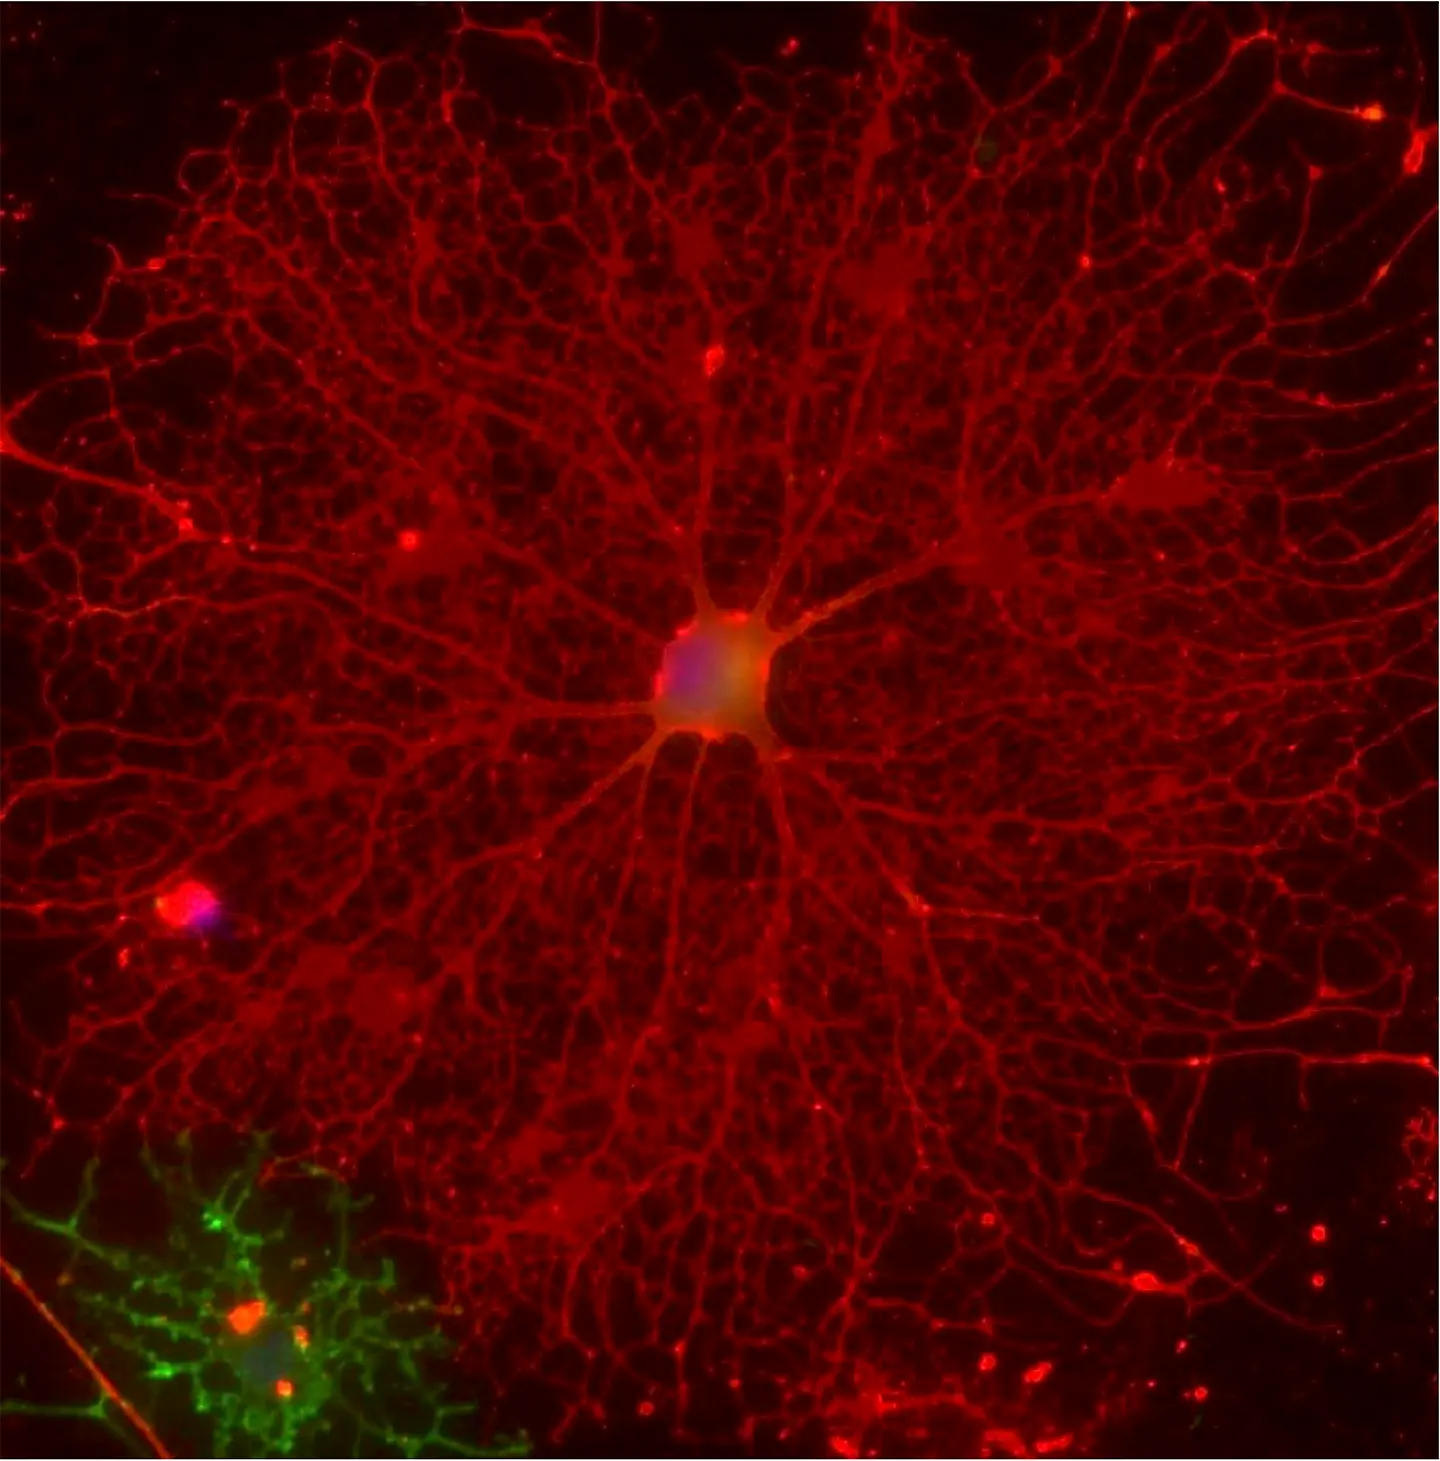

Culturing oligodendrocytes on laminin-411 markedly promoted the formation of branched cellular processes necessary for myelin sheath formation.(Sasaki et al., 2025, Glia: doi: 10.1002/glia.70027, Licensed under CC BY 4.0)

“Building on the findings from our previous studies, we focused on the expression and function of alpha chains of LM, namely α1, α2, α3, α4, and α5, in this study,” says Suzuki, sharing further insights about the study. Thereafter, the scientists utilized artificially produced ‘recombinant’ proteins made from the α1, α2, and α4 chains of LM to identify the exact protein fragment that supports myelination by OLs. Results obtained via western blotting and immunocytochemistry—techniques to detect specific proteins within cells—indicated that LM-411 (artificial protein made from the α4 chain of LM) promoted the differentiation of OLs and the formation of the myelin membrane.